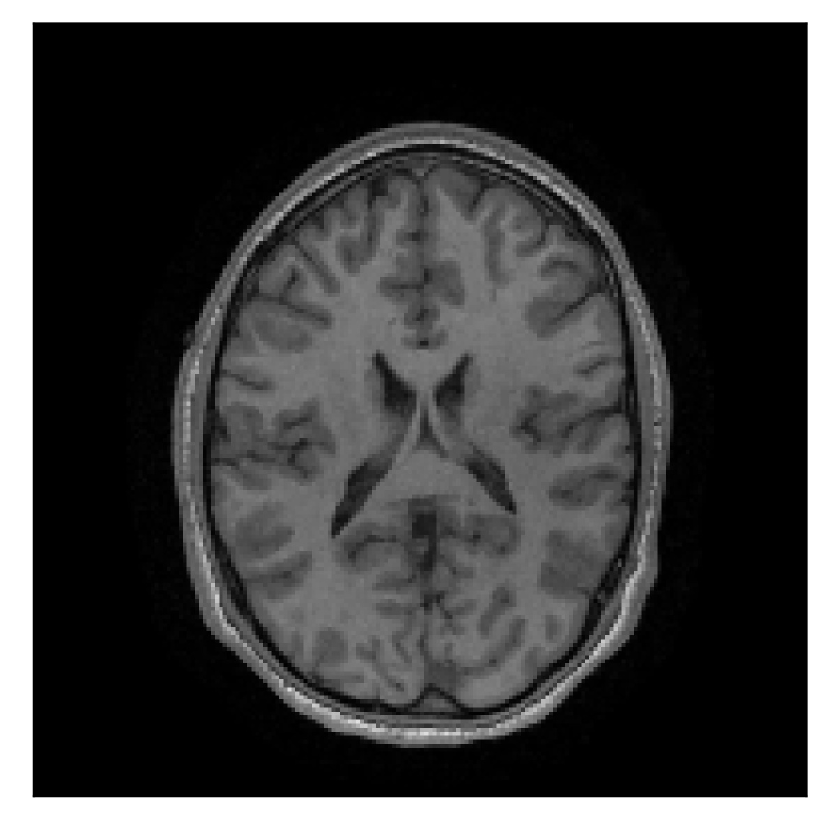

4.3 Experiment 3: scanner reconstruction vs raw k-space data

The results of the two experiments described in Section 3.3 are depicted in Figures 12 and 14. The main difference between the two experiments is related to the input data for the proposed motion-correction algorithm.

In the first experiment, the corrupted contrast has been acquired with a protocol based on a linear filling pattern in -space. Note that, in this particular case, the scanner reconstruction implements the SENSE method. We then extracted the DICOM of both amplitude and phase produced by the scanner, and used it as input data (after a Fourier transform) for the algorithm. The proposed scheme is able to successfully remove the motion artifacts in Figure 12.

In the case of randomized sampling, the scanner reconstruction is not adequate as input data for the proposed motion-correction algorithm, because it employs a compressed-sensing algorithm. We speculate that compressed-sensing reconstructions degrade the information contained in the corrupted volume, and the corrected contrast cannot be effectively recovered by simply removing rigid-motion artifacts (we defer the degraded results when using scanner reconstruction data in Appendix A). However, when the input data is obtained by directly processing the raw -space data via the SENSE reconstruction, the motion-correction scheme is able to successfully remove the motion artifacts (Figure 14).

| Section 3.3, Figure 12 | Sagittal | 22.26 | 27.54 | 0.6963 | 0.8409 |

| Coronal | 23.46 | 31.65 | 0.7321 | 0.8370 | |

| Axial | 24.55 | 32.33 | 0.7895 | 0.8144 | |

| Section 3.3, Figure 14 | Sagittal | 24.72 | 28.76 | 0.6762 | 0.7818 |

| Coronal | 25.95 | 29.54 | 0.7238 | 0.8107 | |

| Axial | 25.08 | 29.59 | 0.7263 | 0.8407 | |

| Section 3.3, Figure 12 | T2 | Completely corrected | No blurring | No additional artifacts | |

| Section 3.3, Figure 14 | T2-FLAIR | Completely corrected | Some blurring | No additional artifacts | Good grey white matter differentiation |